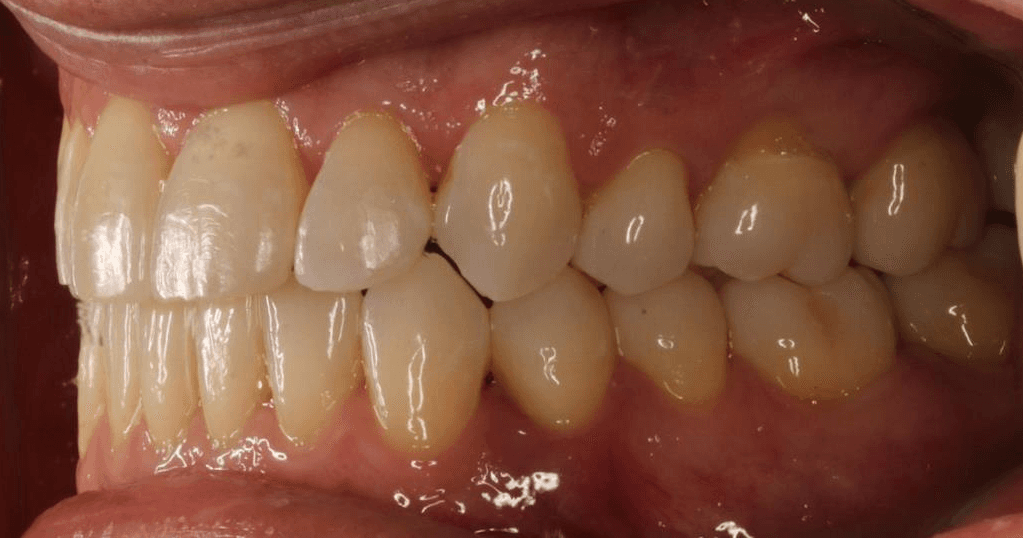

Final results

INTRAORAL